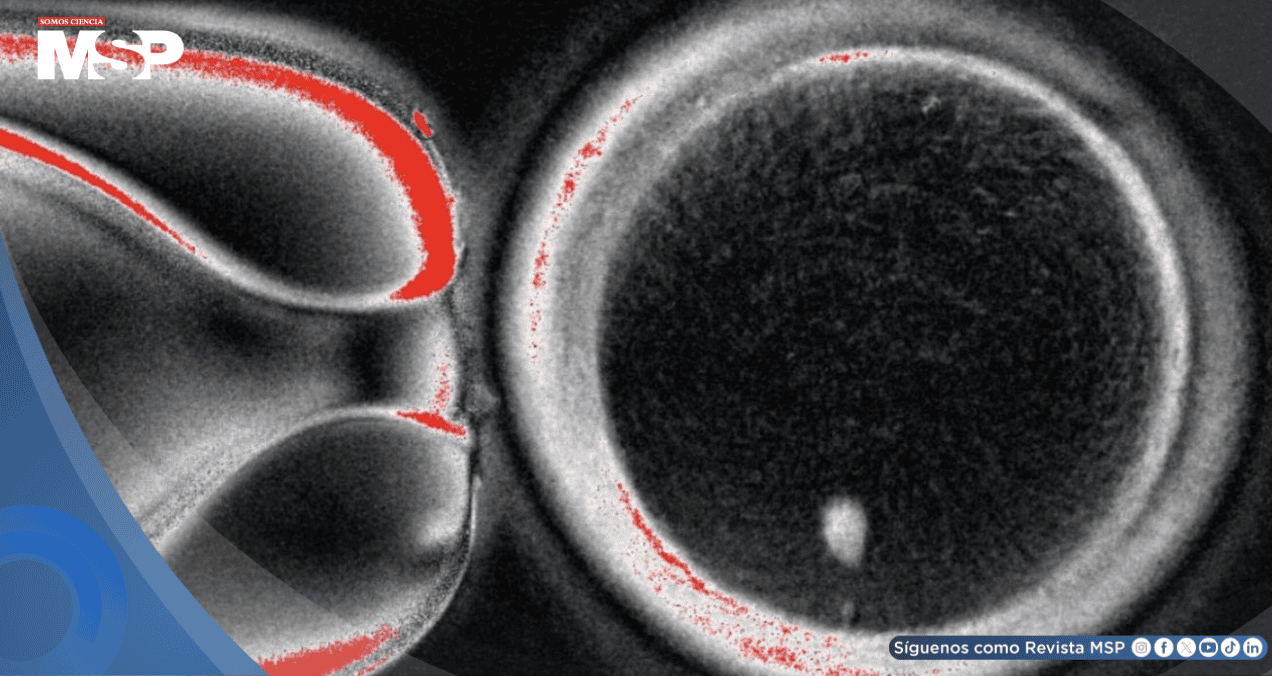

El equipo consiguió obtener 82 óvulos funcionales que fueron fecundados con esperma humano. De ellos, un 9% alcanzó la fase de blastocisto, correspondiente a los primeros seis días de desarrollo embrionario. Aunque ningún embrión se cultivó más allá de ese punto, los investigadores consideran que se trata de una prueba de concepto válida.